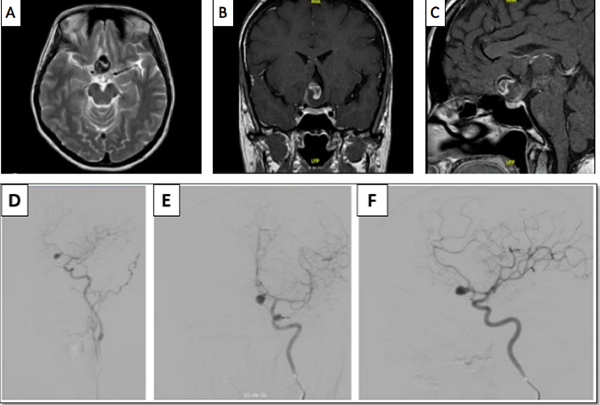

Luego del análisis del caso, y teniendo en cuenta la presencia del trombo intracavitario, el cuello del aneurisma, la posición favorable del saco aneurismático, y la edad de la paciente, se decidió que la cirugía era la mejor opción terapéutica, se realizó una craneotomía pterional derecha, y un abordaje transilviano bajo visión microscópica. Se encontró un aneurisma de gran tamaño dependiente de la AcomA (Figura 2), con dirección anteroinferior, calcificación en las paredes del domo y signos de trombosis. Una vez se identificó el cuello, y ambas A1 y A2, se posicionó un clip recto de 9 mm, que luego se reacomodó con otro clip definitivo de 9 mm, se retiró el previamente colocado, quedando con un solo clip definitivo. A continuación se comprobó la permeabilidad de los vasos A1 y A2, así como de la arteria recurrente de Heubner ipsilateral con doppler intraoperatorio. Se procedió con la disección del domo del aneurisma y trombectomía con aspirador ultrasónico, dejando el interior del aneurisma friable, y descomprimiendo de esta manera el nervio y el quiasma óptico. El procedimiento finalizó sin complicaciones, la paciente mejoró del déficit en el postoperatorio inmediato, y se llevó a arteriografía de control al día siguiente de la intervención, con la que se confirmó el adecuado clipaje de la lesión (Figura 3).

Figura 3. Arteriografía de control postoperatoria (A y B), en la que se observa adecuada exclusión de aneurisma cerebral